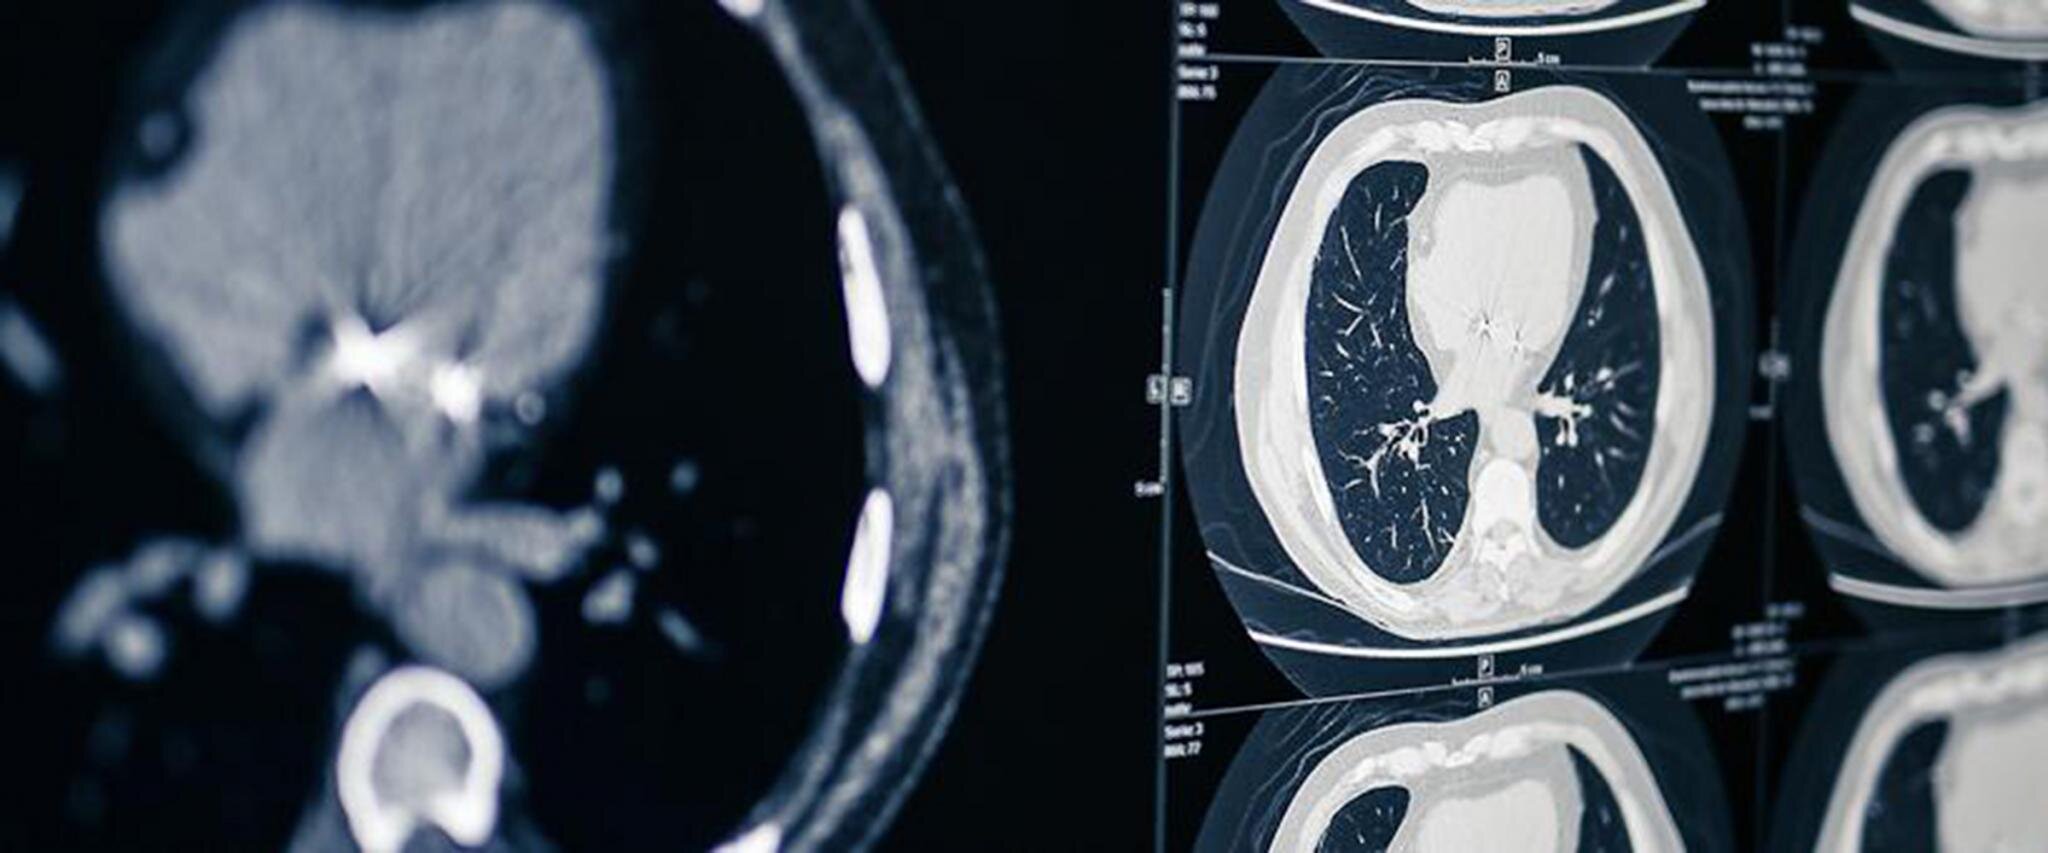

Die kardiothorakale Radiologie befasst sich mit den Organen des Brustkorbes. Dazu gehören u.a.:

In enger Zusammenarbeit mit Ihren behandelnden Ärztinnen und Ärzten wählen wir die für Sie passende Untersuchungsmethode. Neben dem „einfachen“ Röntgenbild können auch mit der Computertomographie (CT) oder Magnetresonanztomographie (MRT) Bilder der Lungen oder des schlagenden Herzens gemacht werden.